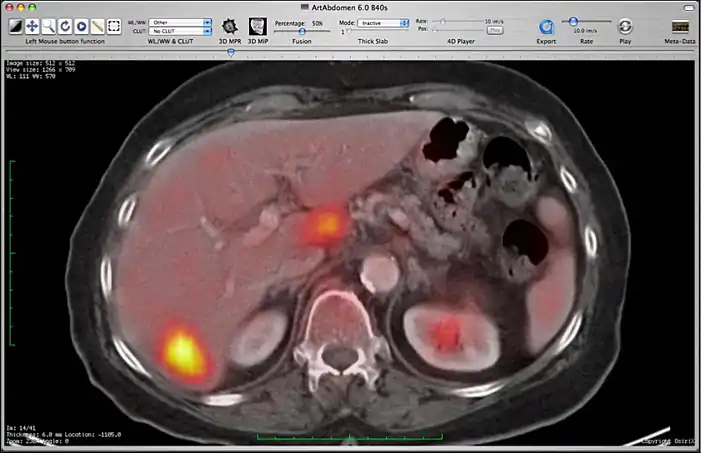

Image fusion between a CT and PET series.

You can control the fusion intensity with the “Fusion Percentage” slider from the toolbar. Note that if you close one of the two series, the fusion will be stopped. If you make a modification on the first series (CLUT, zoom, rotation, ...), these modifications will be applied to the second one.

Image fusion is also available for 2D and 3D reconstructions implying that you can use image fusion along with MPR, Volume rendering, etc...